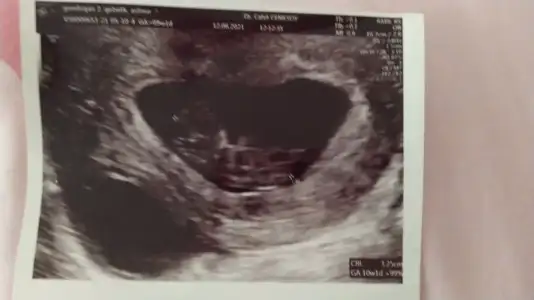

İkra meyra bunada bakarmısın bana bakmıştın daha önce ve tuttu kızım oldu buda görümcem in bunada bakarmısın lütfen 🤗

• IMG-20210612-WA0012.webp

IMG-20210612-WA0012.webp

53,3 KB · Görüntüleme: 52